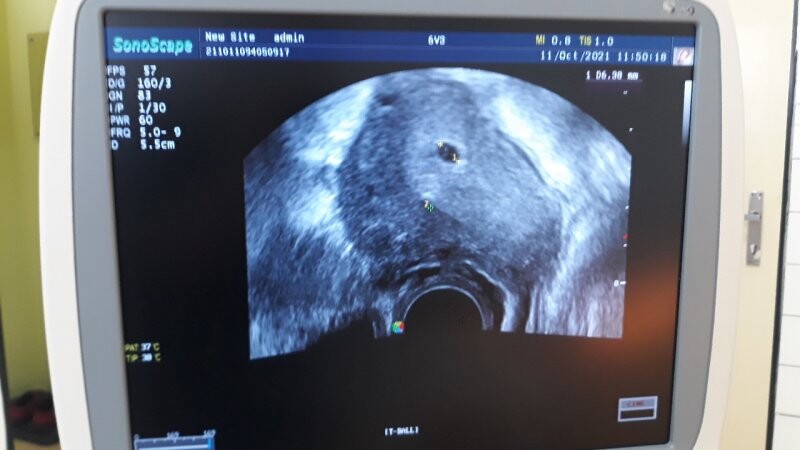

Dobrý den, chci se zeptat, co znamená dvojka na ultrazvuku viz foto. Děkuji

takto těžko hodnotit bez možnosti komplexního ultrazvukového vyšetření, nicméně to vypadá, že lékař jen omylem "odkliknul" další značku, která nic neznamená. Pro Váš klid se při další kontrole optejte, zda je vše v pořádku.